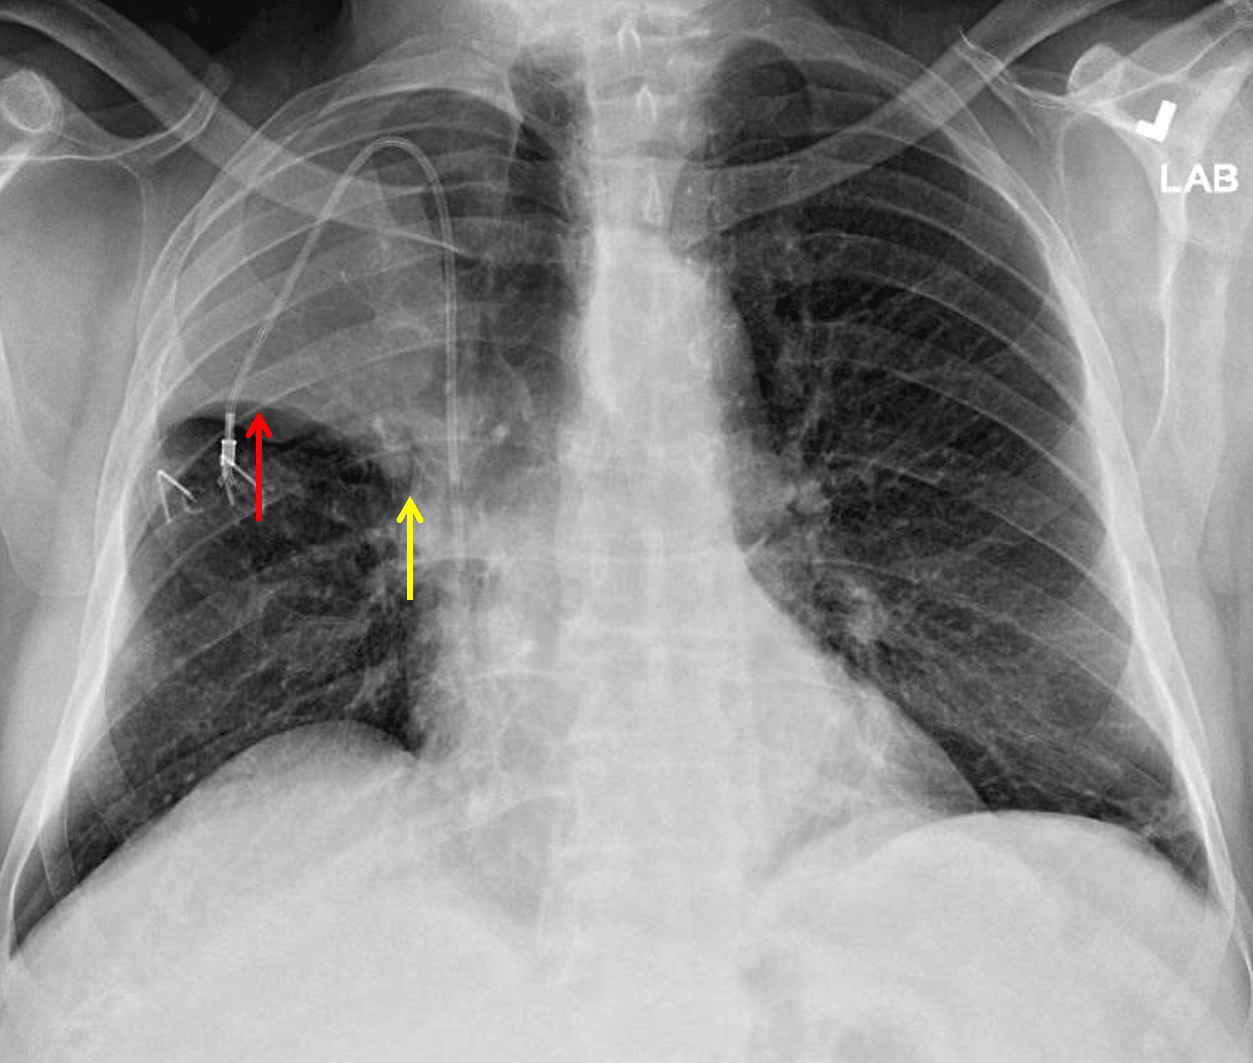

Right upper lobe collapse. The minor fissure is elevated laterally (red arrow) but not as elevated centrally (yellow arrow) raising concern for a perihilar mass.